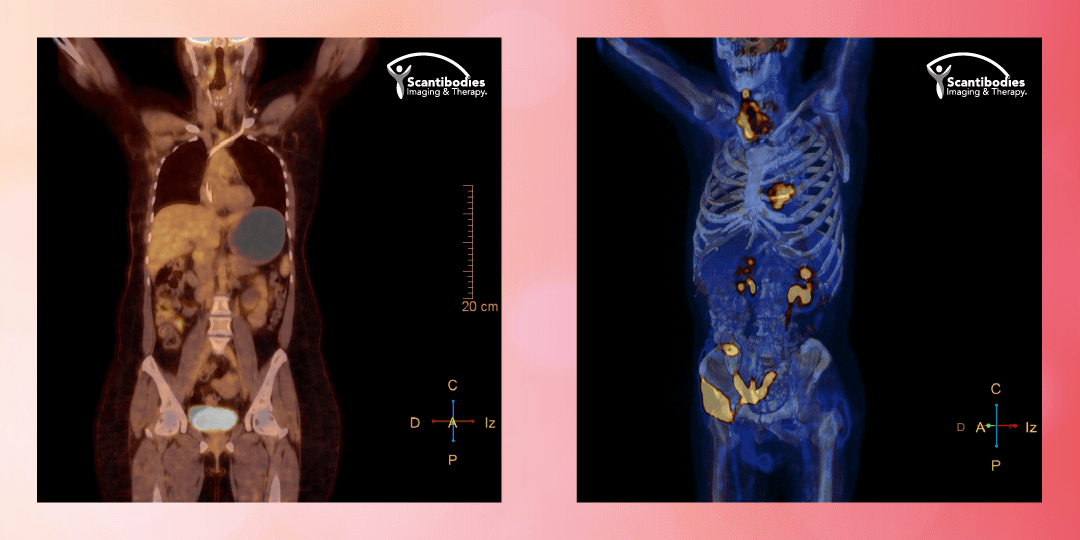

PET CT - Tomografía por Emisión de Positrones:

El PET es un estudio de diagnóstico funcional, rápido y preciso, con resultados de confirmación diagnóstica y monitoreo de la enfermedad. Siendo el PET CT estudio de cuerpo completo, se determina la localización y extensión de la enfermedad, dando información importante al especialista para determinar el tratamiento adecuado.